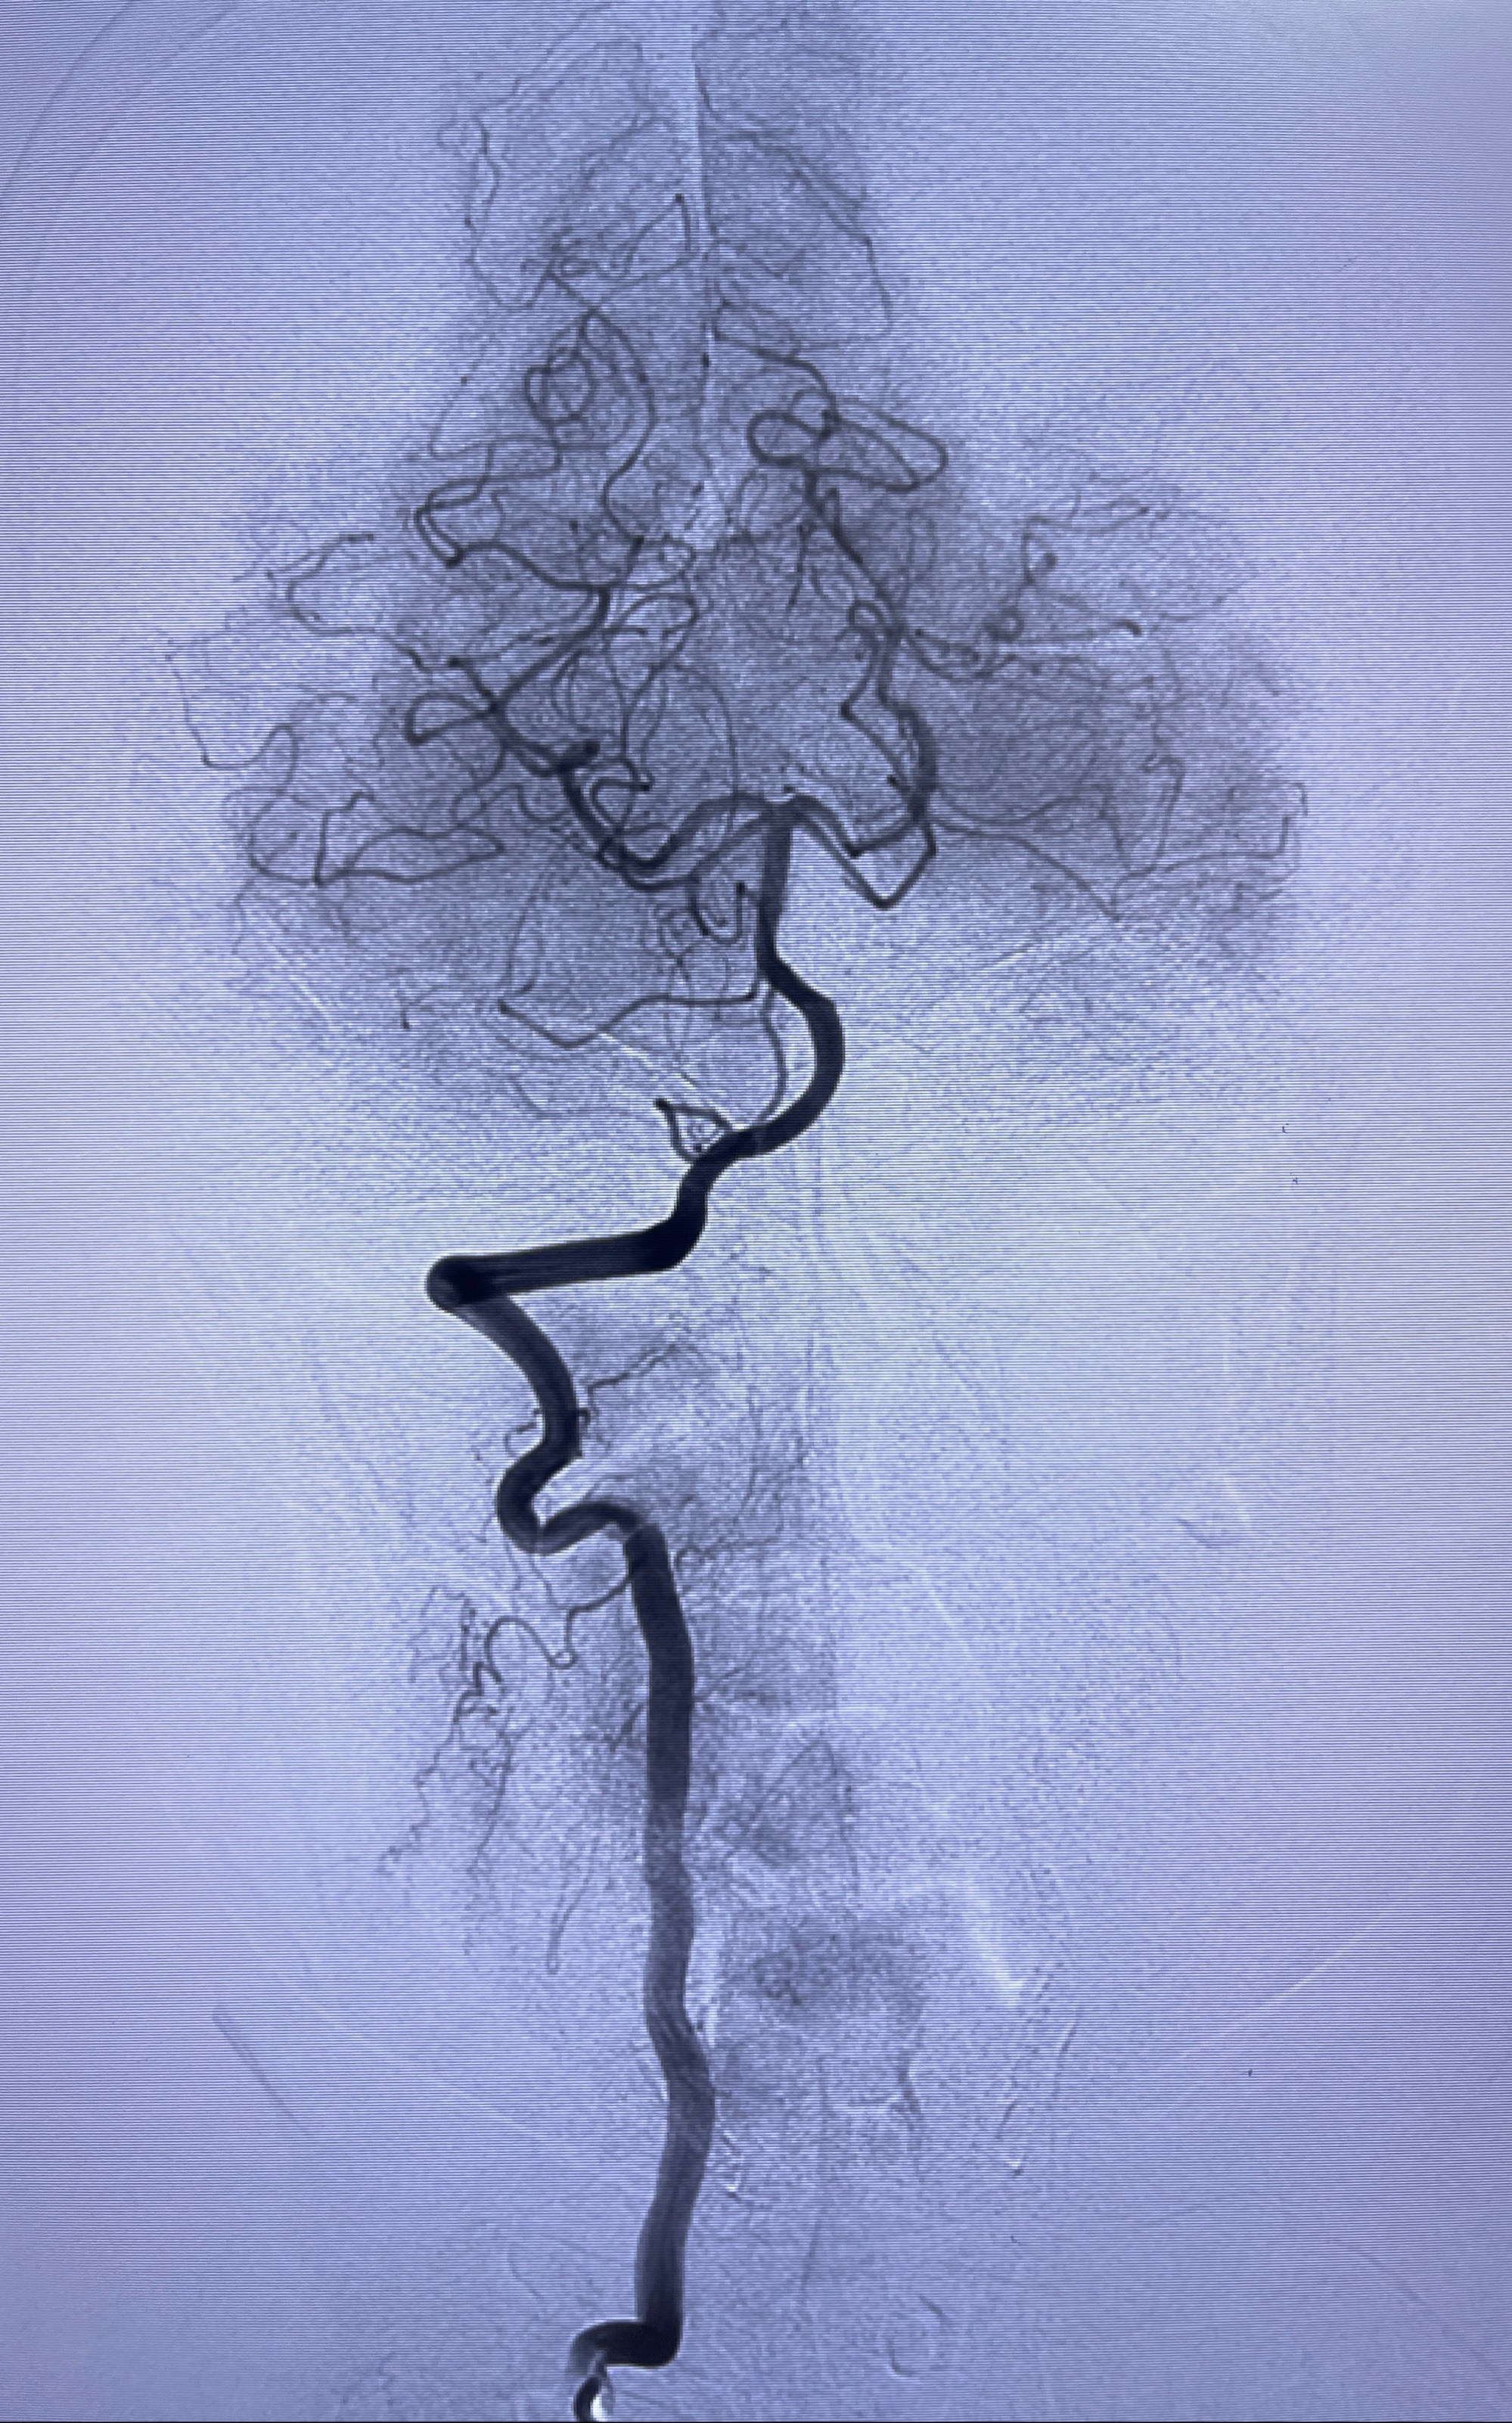

术后3D显示支架贴壁佳

麻醉苏醒佳,遵嘱活动!视力视野正常。